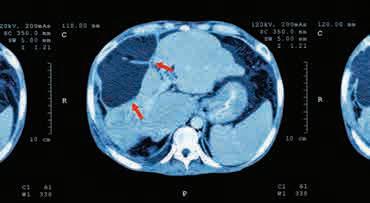

треби X-зрака и техници томографског снимања уз употребу рачунара. Тачније, то је трансмисиона компјутерска томографија